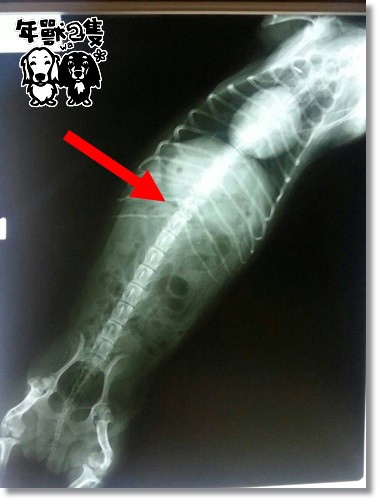

醫生看片後,跟我們說是椎間盤問題沒錯

她的胸椎10-11節之間的間距變窄,壓迫到神經了

拍了片後,更篤定她就是椎間盤的問題呀~~~!!!

但,醫生仍是說她算很輕微